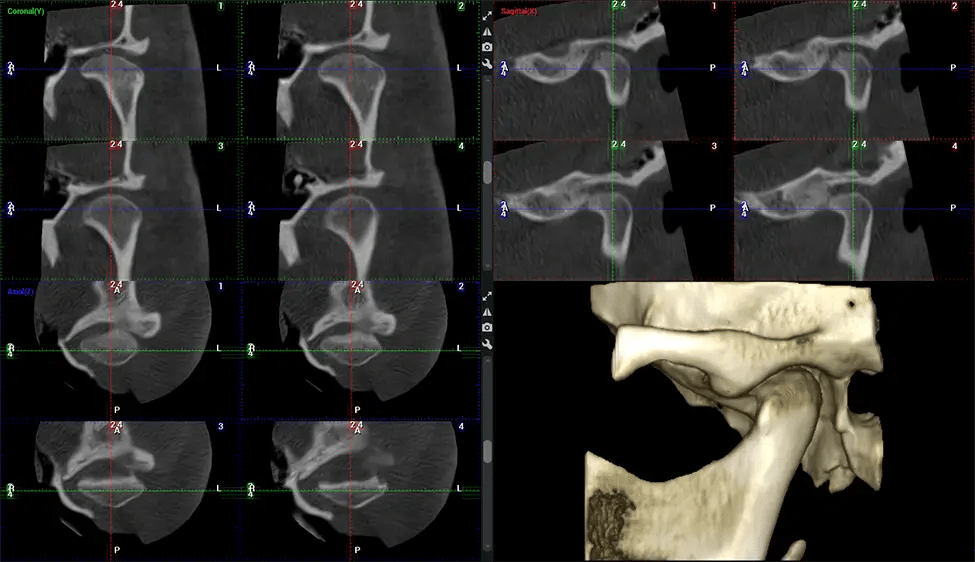

Esta exploración 3D, llamada tomografía computarizada de haz cónico, le brinda a su dentista una imagen más completa de su anatomía bucal y sus procesos patológicos que una radiografía tradicional. A diferencia de las radiografías convencionales, que capturan una imagen 2D de la boca desde varios ángulos, una exploración 3D toma varias radiografías digitales para una imagen. Proporciona una vista completa de la mandíbula, los dientes, los nervios y los tejidos blandos. Esta vista mejorada permite a los dentistas detectar problemas menores que no son visibles en las exploraciones 2D tradicionales, como muelas del juicio impactadas o fracturas óseas en la cavidad sinusal.

Existen muchos beneficios al utilizar la tecnología CBCT, especialmente en comparación con el formato tradicional de rayos X 2D. Una de las ventajas más importantes de las exploraciones CBCT es que proporcionan mucha más información que las radiografías tradicionales. Una exploración le permite a su dentista ver imágenes desde todos los ángulos de su mandíbula y boca, incluidos los senos nasales, la cavidad nasal, los pómulos y otras áreas circundantes. Esta información adicional ayuda a su dentista a elaborar un plan de tratamiento integral que aborde todos los aspectos de su salud bucal.

Primero se coloca al paciente en el escáner CBCT, que normalmente consta de un brazo giratorio que alberga la fuente de rayos X y un detector. La cabeza del paciente está inmovilizada para garantizar una captura de imágenes precisa. La fuente de rayos X y el detector giran alrededor de la cabeza del paciente, capturando varias imágenes de rayos X desde múltiples ángulos. A medida que la fuente de rayos X gira, emite un haz de rayos X en forma de cono hacia el detector. El detector captura las imágenes de rayos X, que luego son procesadas por el software CBCT.

Después del proceso de escaneo, las imágenes de rayos X capturadas son procesadas por el software CBCT, que aplica algoritmos para reconstruir una imagen 3D detallada del área escaneada. El software recopila estas imágenes de rayos X individuales y crea una representación digital en 3D de la anatomía del paciente. El dentista o el radiólogo pueden ver y analizar la imagen CBCT 3D reconstruida. Esta imagen se puede manipular, rotar y acercar o alejar para examinar estructuras específicas y evaluar la condición del paciente.

Planmeca Viso G7 CBCT (Cone Beam CT Scan) está diseñado para superar las demandas de los líderes de la industria, los especialistas y las grandes instituciones. Tiene un gran sensor de ø25×30 cm con cuatro cámaras integradas. Puede capturar tamaños de volumen ilimitados, desde ø3×3 cm hasta ø30x30cm, capturando el casquete escutelario a través de C7 en la columna cervical. Planmeca Viso G7 ofrece el escaneo de volumen único más grande de la industria de ø30×19 cm. Está preparado para manejar modalidades de imágenes avanzadas como la tecnología Planmeca ProFace® y Planmeca 4D™ Jaw Motion. El soporte occipital para la cabeza permite una visión sin obstáculos del tejido facial.